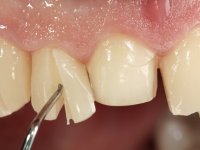

Realizado o diagnóstico e tomada a decisão quanto ao tratamento a executar, tornou-se importante definir qual a sequência de trabalho a adotar no sentido de conseguir a reabilitação da D.V.O. (V.D.O), de forma progressiva e equilibrada. Na primeira fase fez-se uma pré-impressão da arcada inferior com silicone tipo “putty” e em seguida realizou-se o preparo dentário de todo o sector posterior. O preparo para os overlays foi feito coronalmente à linha amelo cementaria no sentido de ser o mais conservador possível. A impressão foi feita com técnica de dupla mistura após afastamento gengival realizado com pasta de caulino. A provisória foi realizada com resina composta de polimerização dual. Em laboratório foram realizados os overlays após se ter aberto ligeiramente (1,5mm) a D.V.O. nos modelos montados em articulador semi-ajustável. Simultaneamente o sector antero-inferior foi encerado no sentido de acompanhar este aumento da D.V.O. Também foi confecionada uma chave de silicone translucido para posterior confeção dos provisórios antero-inferiores. Em boca foi primeiro realizada a provisionalização dos dentes anteriores utilizando resina composta previamente aquecida após preparação das superfícies dentárias para a adesão. Foi colocado o dique de borracha para promover o isolamento absoluto e posteriormente foram colados os overlays. Em laboratório foi realizada nova chave de silicone para confecionar os provisórios antero-superiores. Seguidamente em boca foram preparados os seis dentes antero-superiores após colocação do fio de afastamento gengival. Feita a preparação adequada das superfícies dentárias foi realizada a impressão com técnica de dupla mistura e a respetiva provisória. Em laboratório foram confecionadas 6 facetas feldespáticas num modelo de trabalho tipo “Geller”. A provisória foi removida e as facetas foram coladas em boca utilizando um isolamento relativo competente. Esta opção foi tomada em virtude de uma prévia experiencia negativa com a colocação do dique de borracha na mandibula. Após a colagem dos laminados antero-superiores foram dadas 12 semanas para avaliar a adaptação do paciente à nova situação e então iniciar a confeção das facetas antero-inferiores. Após colocação do fio de afastamento gengival. foram feitos os preparos dentários adequados e em seguida foi feita a impressão. Também foi feita a preparação do dente 3.4 que, entretanto, tinha sofrido uma fratura do overlay. As facetas e a restauração do 3.4 foram realizadas num modelo de trabalho tipo “Geller”. Após remoção da provisória, as facetas foram coladas em boca, utilizando um isolamento relativo pelas razões apontadas anteriormente. Após colocação do trabalho o paciente foi reabilitado por outros colegas com um implante na zona do 2.6 e substituição da coroa aparafusada sobre o implante colocado no local do 3.5. Posteriormente surgiram fraturas nos overlays dos dentes 4.7 e 3.7 que foram reabilitados com overlays em Zr.